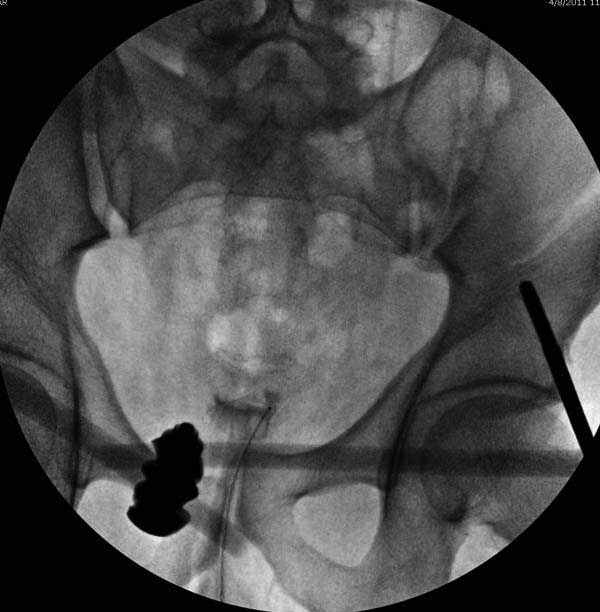

Здесь представлен случай 38 летнего больного (падение с высоты 9 метров) с нарушением тазового кольца. При поступлении для стабилизации передне-нижний аппарат наружной фиксации и на 6й день, вчера, операция из двух доступов.

Наружные фиксаторы создают не только стабильность костей таза, а также в экстренных случаях помогают уменьшить обьем таза в профилактике кровотечения!

Представлены снимки техники проведения стержней. Через место прикрепления прямой мышцы в Inferior Iliac Spine в направления вырезки создается жесткость. Weber clamp изнутри таза для репозиции, и фиксация после репозиции перелома крыла подвздошной кости. Наружный аппарат удален, нагрузка предполагается через два месяца.